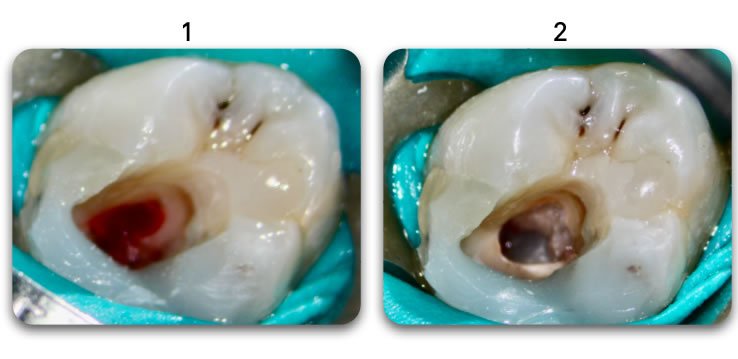

Excellent light transmission

Excellent light transmission for use with dual-cure resins, Biolight DUAL offer excellent light transmission through the optic fiber material.